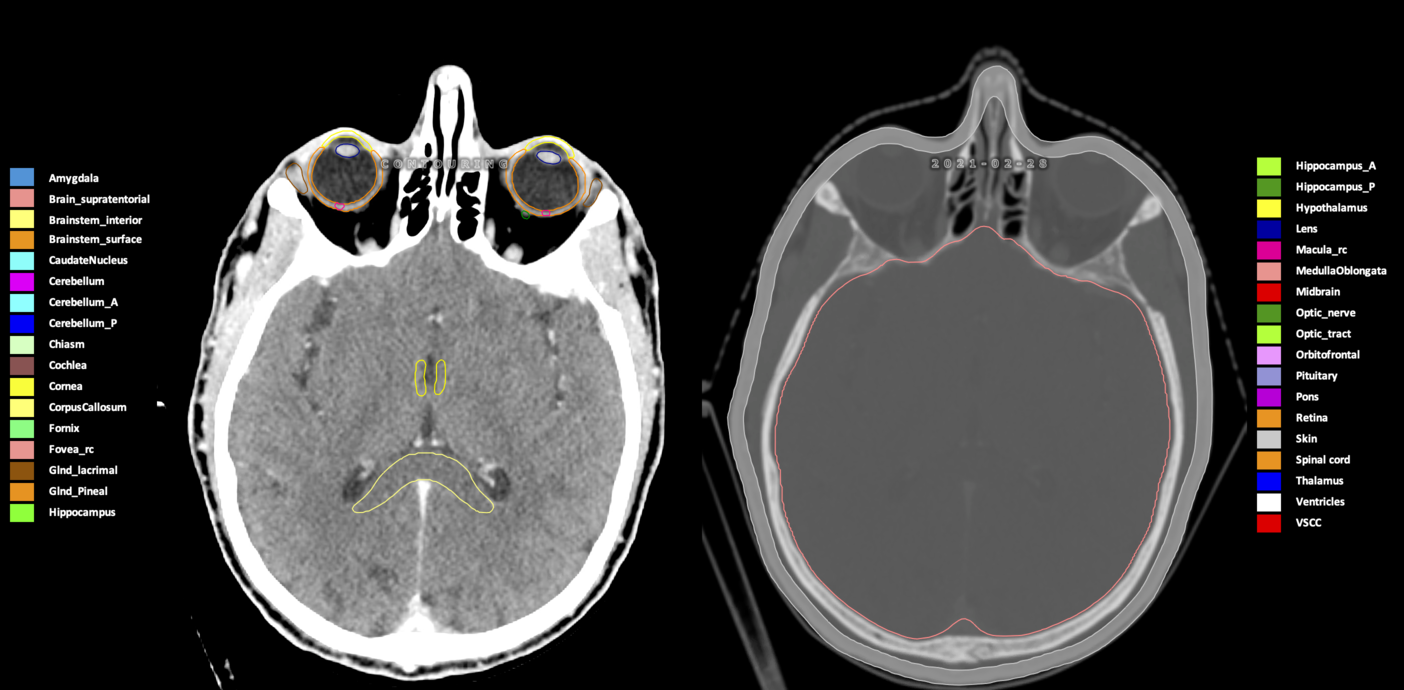

Included are all OARs known to be relevant for radiation-induced toxicity in neuro-oncology: brain, brainstem (midbrain, pons, medulla oblongata), chiasm, cerebellum (anterior & posterior), cochlea, cornea, hippocampus (anterior & posterior), hypothalamus, lens, lacrimal gland, optic nerve, pituitary, skin, and vestibular & semicircular canals. To further facilitate research on cognition, vision and radiological changes after irradiation of the brain, potential clinically-relevant OARs are included: amygdala, caudate nucleus, cerebellum (anterior & posterior), corpus callosum, fornix, macula, optic tract, orbitofrontal cortex, periventricular space (PVS), pineal gland, and thalamus.

Three-dimensional delineation of the 25 consensus OARs for neuro-oncology are shown on CT (WW/WL 120/40, 3000/600), 3T MR images, (T1Gd, T2FLAIR 1mm) and 7T MR (MP2RAGE 0.7 mm). All are presented in transversal, sagittal and coronal view.